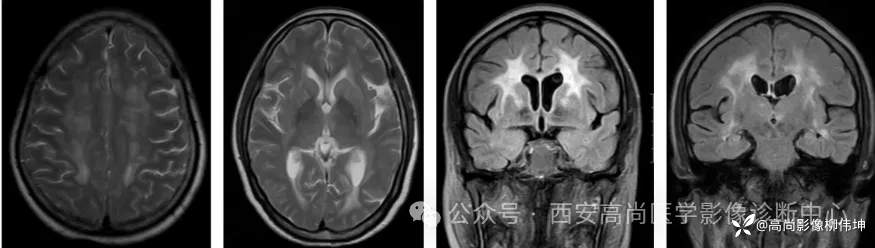

03 影像表现

(1)皮髓质交界区曲线样DWI高信号

为从额顶颞叶皮髓质交界区开始,随着病情发展向大脑后部延伸,形成皮质下“鸡冠花样”或“绸带征”的DWI高信号(具有一定的特异性,病理证实为海绵样变)。家系NID患者仅有37.5%出现上述DWI改变。

(3)对称性脑白质病变

显著累及放射冠和半卵圆中心部位的白质病灶。

(4)皮质肿胀和增强

部分患者在病程的某些阶段出现沿皮质分布的DWI和FLAIR高信号,常伴随沿皮质表面的线样强化(可能与亚急性炎症发作相关),通常分布在后部皮质,且多在临床急性发作期出现,因而要注意和MELAS鉴别。

(5)广泛的脑萎缩和沿小脑中轴对称分布的小脑白质病变影像表现新进展

04 鉴别诊断

伴皮质下和白质脑病的常染色体显性遗传性脑动脉病(CADASIL):是一种成年发病的显性遗传性小血管病,致病基因定位于19p12的Notch3基因.影像上常表现头白质高信号、腔隙性梗死、脑微出血。特征性的颞极白质高信号(0’Sulliva征)和外囊高信号(“人”字征)是诊断CADASIL影像学标志。

MELAS:本病为母系线粒体遗传性疾病,发病年龄10-40岁,临床上以卒中样发作MELAS:为特点,病灶主要累及大脑后半部的颞枕叶皮层或皮层下白质,病灶具有对称性游走性,急性期区域多呈高灌注,MRS倒置乳酸峰具有高度敏感性,多伴有脑萎缩改变。

克雅氏病:又称皮质-纹状体-脊髓变性。临床上以快速进行性痴呆、肌阵挛、共济失调为主要表现。典型影像学表现为对称或非对称性皮层和(或)基底节区受累,通常不累及中央回,扣带回、角回、楔前叶、额上回及纹状体为主要受累部位,DWI信号随病情进展信号增高,可持续数周,晚期消失,晚期脑萎缩改变。